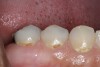

Replacement of existing restorations is responsible for 75% of all operative dentistry.15,19 The reasons for placement and replacement of restorations of direct restorative materials include: primary caries (Figure 1 and Figure 2); recurrent caries (Figure 3); poor margins (Figure 4 and Figure 5); restoration fracture (Figure 6 and Figure 7); tooth fracture (Figure 8); esthetics (Figure 9); non-carious tooth structure lost (attrition, abrasion, abfraction, erosion) (Figure 10); and pain/sensitivity.

Figure 5  Defective margins. Mandibular second molar with a Class II composite resin with a defective facial–gingival margin.

Figure 5